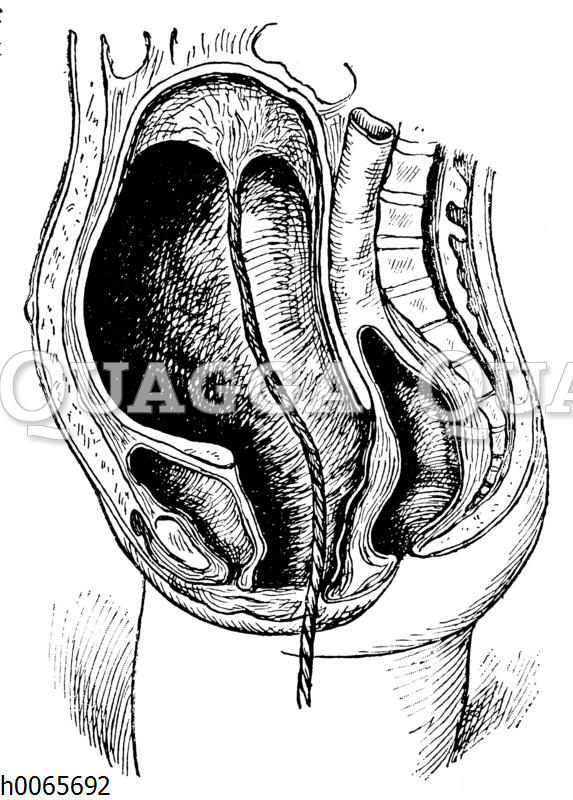

Gebärmutter unmittelbar nach der Geburt: Zeichnung/Illustration/Holzstich – – –

Bildnr.: h0065692

Bildtyp: Holzstich

Erscheinungsdatum: 1911